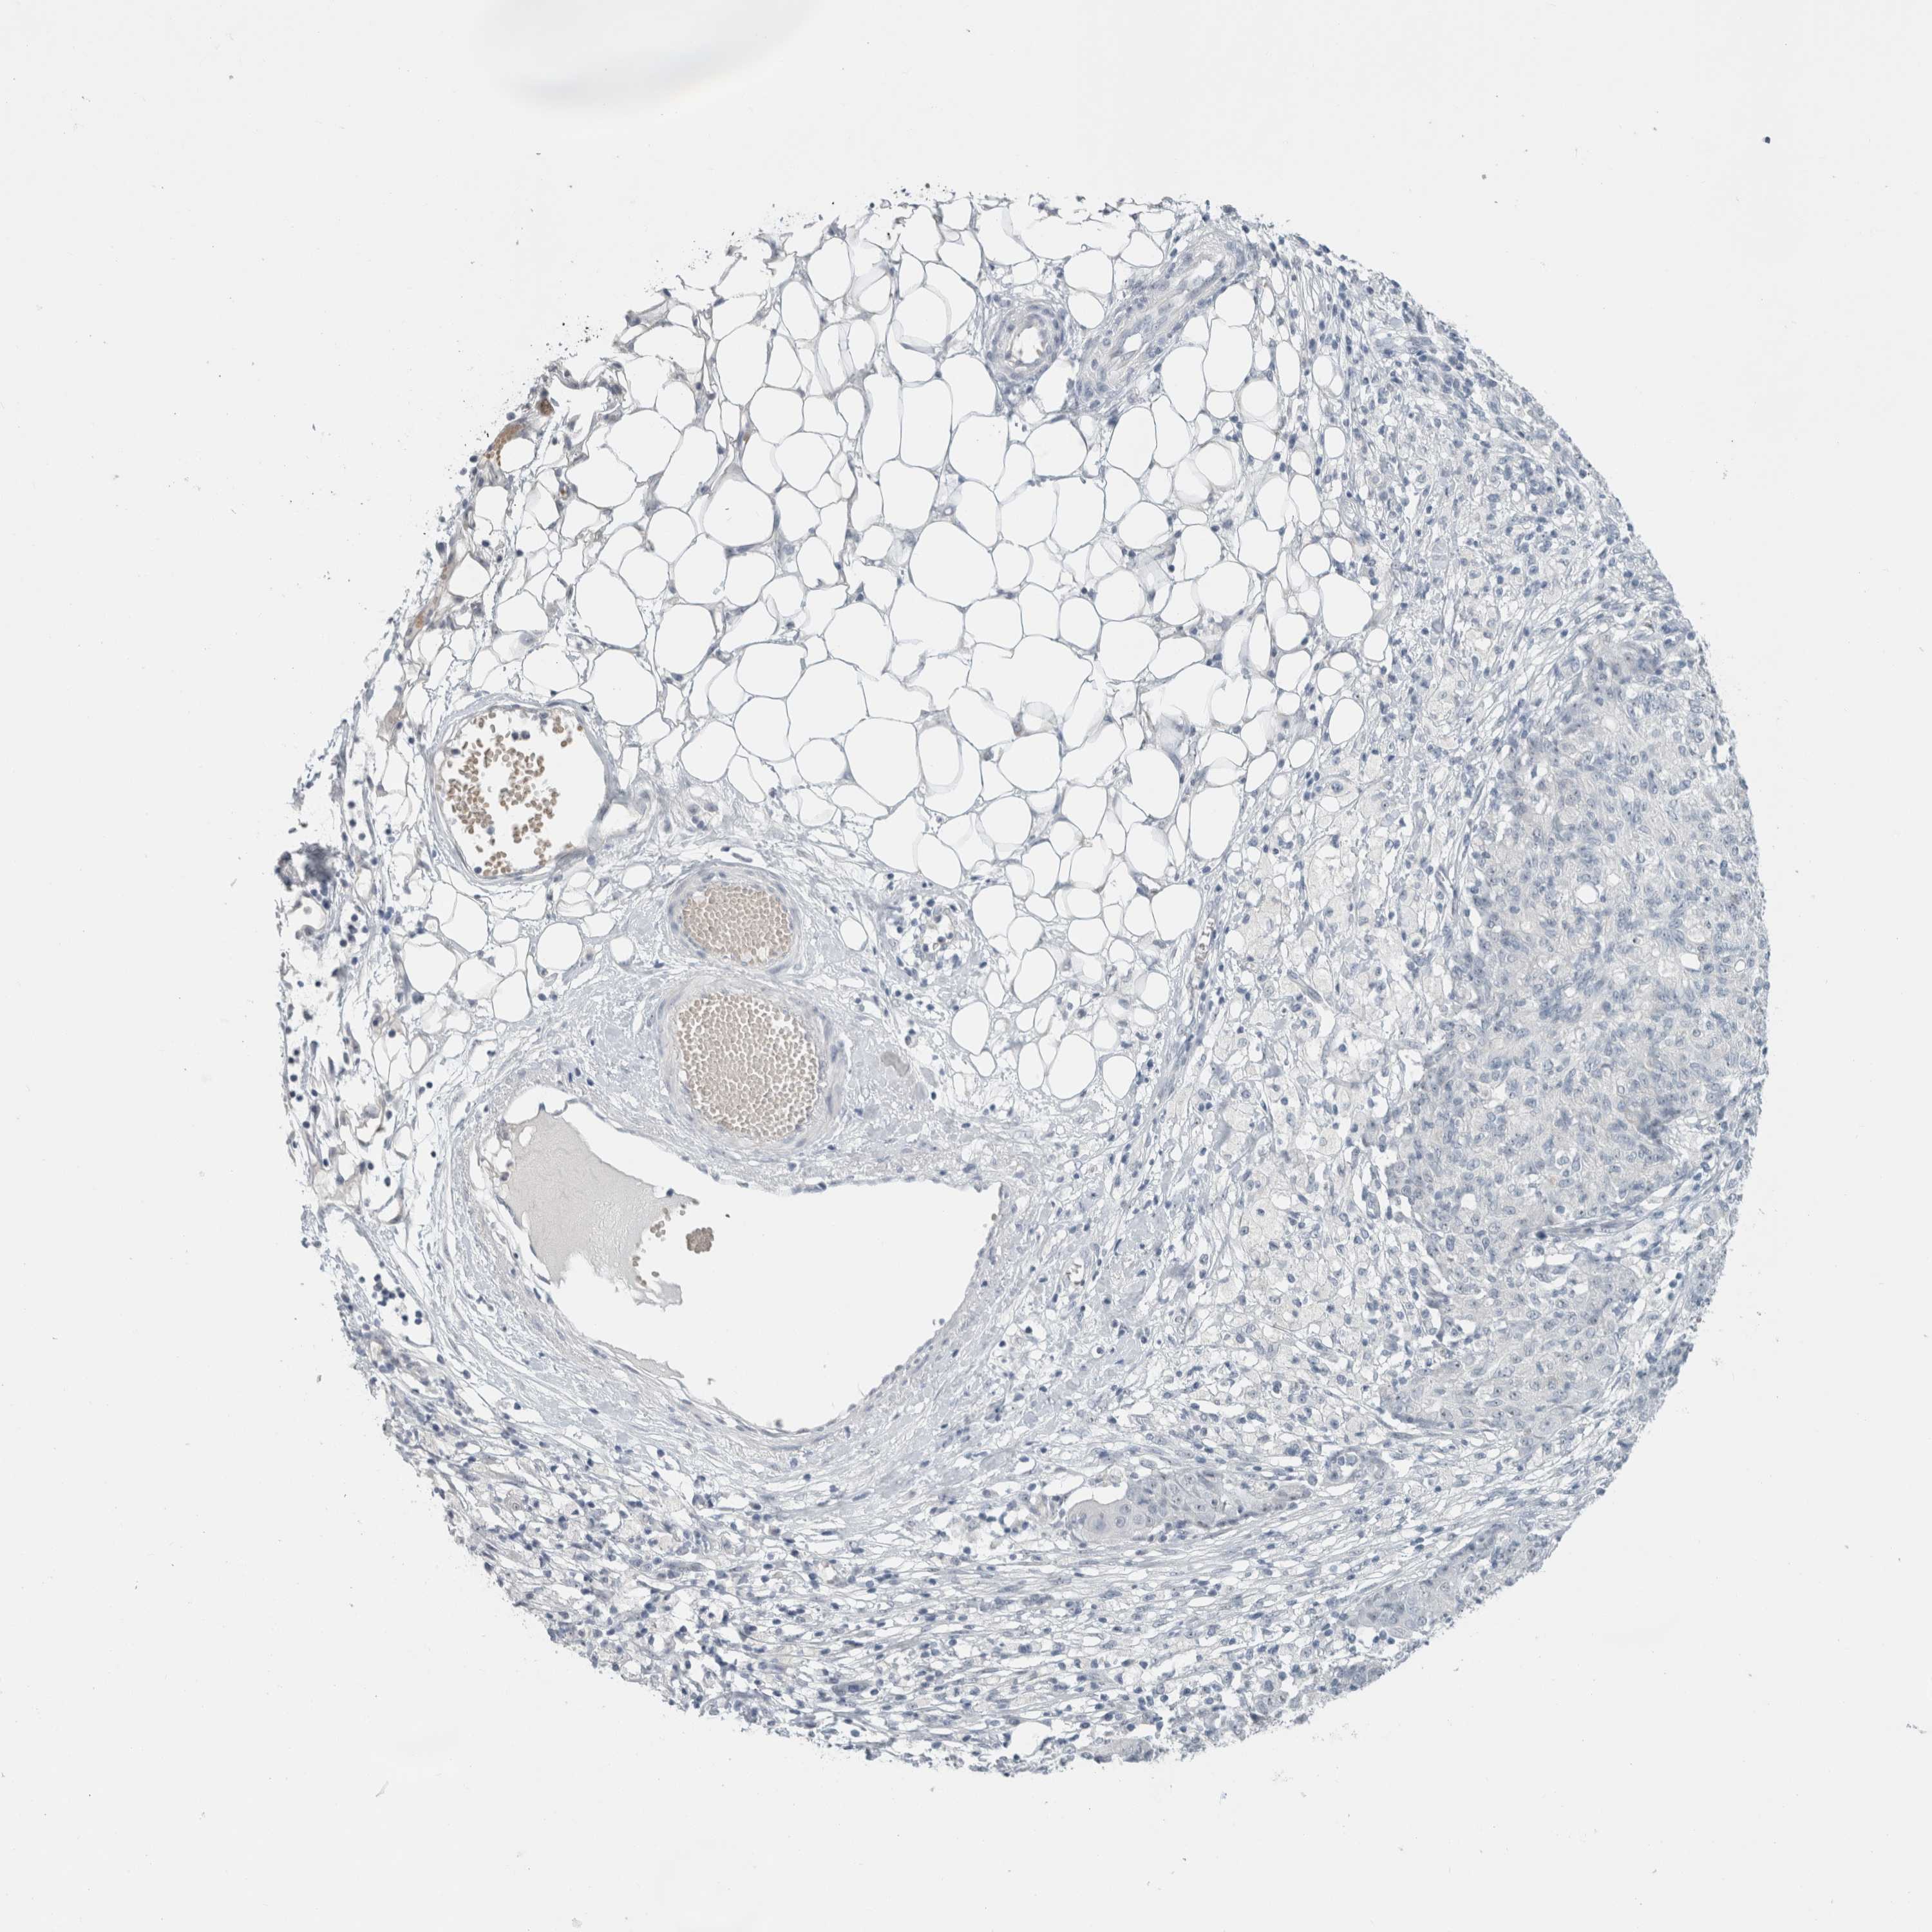

OVARIAN CANCER - Protein expressioni

A mouse-over function shows sample information and annotation data. Click on an image to view it in a full screen mode. Samples can be filtered based on level of antibody staining by selecting one or several of the following categories: high, medium, low and not detected. The assay and annotation is described here.

Note that samples used for immunohistochemistry by the Human Protein Atlas do not correspond to samples in the TCGA dataset.

Antibody stainingi

Antibody staining in the annotated cell types in the current human tissue is reported as not detected, low, medium, or high, based on conventional immunohistochemistry profiling in selected tissues. This score is based on the combination of the staining intensity and fraction of stained cells.

Each image is clickable and will lead to virtual microscopy that enables deeper exploration of all samples and also displays staining intensity scores, fraction scores and subcellular localization as well as patient and tissue information for each sample.

Antibody HPA011284

Antibody CAB026403

Cystadenocarcinoma, serous, NOS

Carcinoma, endometroid

Cystadenocarcinoma, mucinous, NOS

Carcinoma, NOS